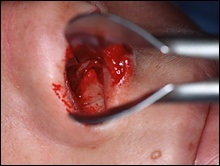

Mielőtt nagyobb acanthion. Ez az, amit úgy néz ki, a művelet során. Az ábrán a jobb ez sárga színű. Acanthion columella található, közvetlenül alatta, ahol a felső ajak határos az alapja az orrát.

Része a gerinc, amelyeket el kell távolítani jelzi a kék vonalon. Removal végezzük vésővel.

A felső és az alsó képen látható két legkiemelkedőbb nazális gerinc, a jobb kilátás bővítették segítségével horgokat.